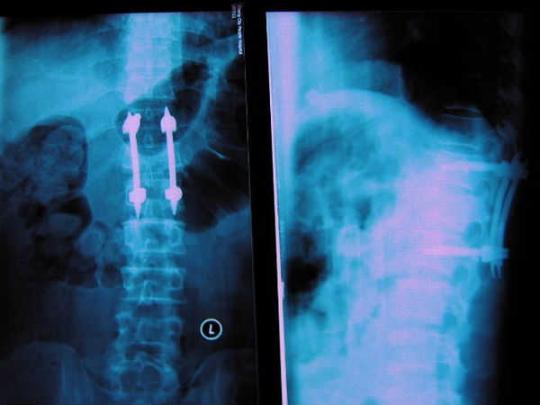

脊柱微创经典内固定技术---经皮椎弓根螺钉内固